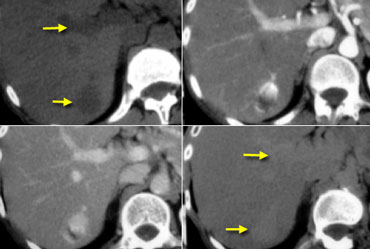

NECT, arterial and portal venous phase in a patient with Hepatitis C with two lesions in the liver (arrows). NECT, arterial and portal venous phase in a patient with Hepatitis C with two lesions in the liver (arrows).

In the arterial phase we see two hypervascular lesions.

Now do not just concentrate on the images, where you see the lesions best.

You have to look at all the other images, because they give you the clue to the diagnosis.

The upper images show a lesion that is isodens to the liver on the NECT.

In the arterial phase there is enhancement, but not as dense as the bloodpool.

In the portal venous phase the lesion is again isodense to the surrounding liver parenchyma and you can't see it.

If you only had the portal venous phase you surely would miss this lesion.

The lower images show a lesion that is visible on all images.

You see it on the NECT and you could say it is hypodens compared to the liver.

Does this help you?

No, not in the least.

However if you look at the bloodpool, you will notice that on all phases it is as dense as the bloodpool.

So we have a HCC in the right lobe on the upper images and a hemangioma in the left lobe on the lower images.

The key is to look at all the phases.